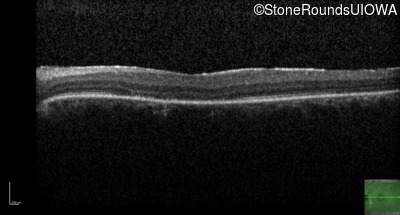

Optical Coherence Tomography - Right - 20/50 -1 sc

Exemplar / OCT Stack